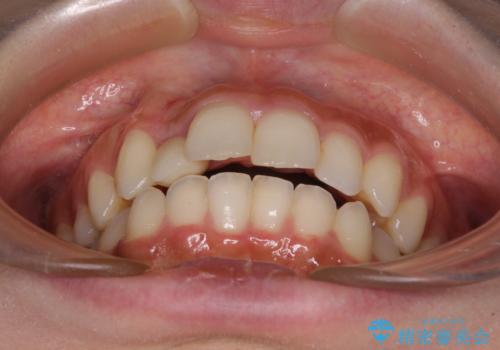

- 上下前歯のデコボコを気にして来院された患者様です。

前歯のセラミックが装着されている歯は、歯根が短くなっており、他院では抜けてしまうので矯正はできないと言われていたようです。

患者様と相談し、抜けてしまった場合にはインプラントあるいはブリッジによる補綴治療が必要となることを確認し、極力歯根に負担のかからないような仕上がりで治療を進めて行くこととしました。

デコボコを解消には、IPR(歯と歯の間を削る)をメインに歯列排列を設計し、インビザラインにて矯正治療を行うこととしました。

レントゲン写真上では、矯正治療前後で歯根長さに大きな違いはなく、抜歯を回避することができました。

上顎内側に転位している前から2番目の歯は移動が難しく、無理矢理歯根全体を動かそうと設計すると、歯肉退縮・歯髄壊死・歯根吸収といった危険性が増すため、無難なゴールにて治療を終えることとなりました。